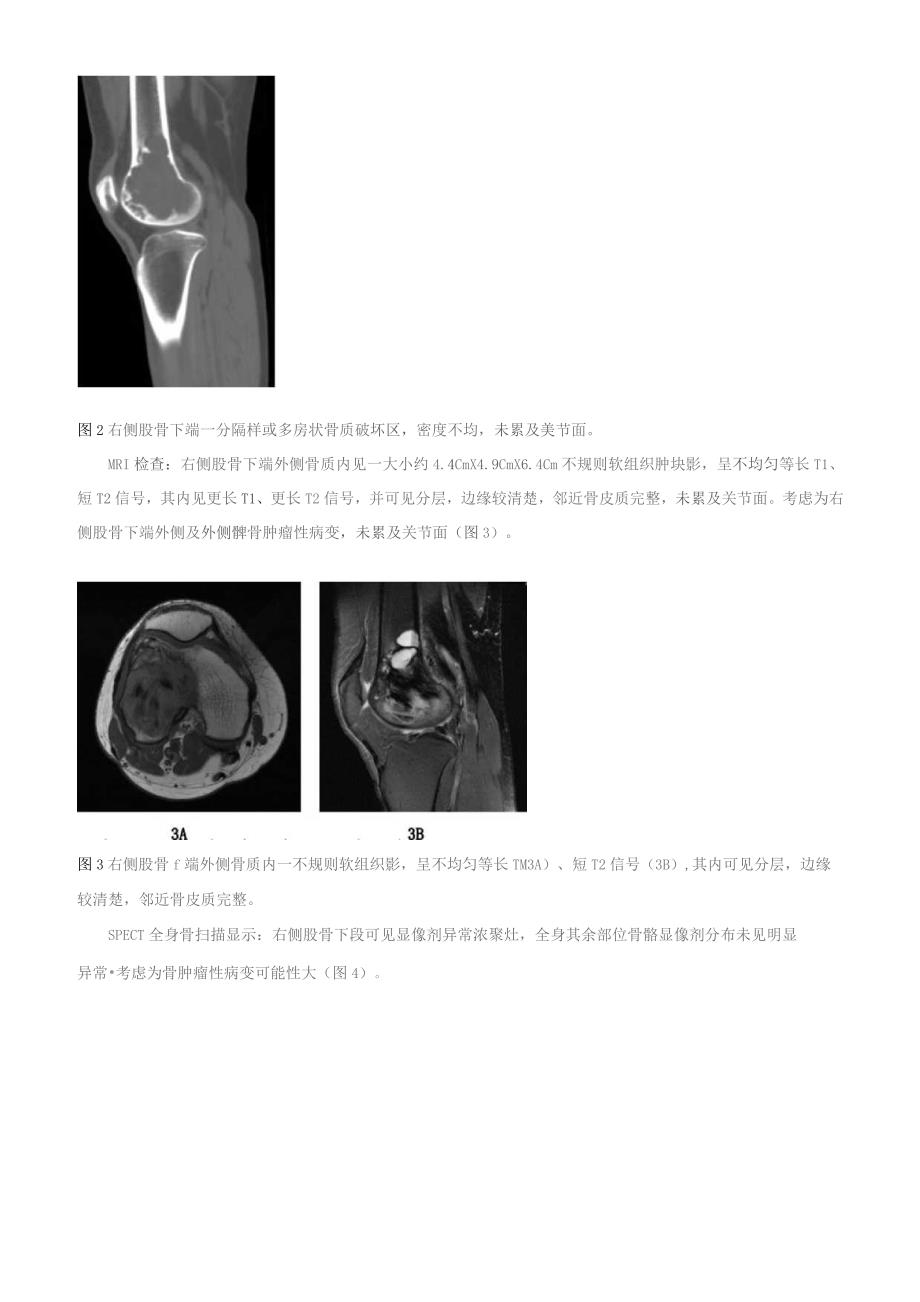

3、骨巨细胞瘤?(图1)。图1右侧股骨下端一密度不均的骨质破坏区,呈多房状改变,未见明显骨膜反应。CT检查:右侧股骨下端偏外侧见一大小约为4.6CnIX3.6Cm的骨质破坏区,密度不均,内见多发分隔,局部呈多房状改变,余无特殊。考虑为右侧股骨下端骨巨细胞瘤可能(图2)。图2右侧股骨下端一分隔样或多房状骨质破坏区,密度不均,未累及美节面。MRI检查:右侧股骨下端外侧骨质内见一大小约4.4CmX4.9CmX6.4Cm不规则软组织肿块影,呈不均匀等长T1、短T2信号,其内见更长T1、更长T2信号,并可见分层,边缘较清楚,邻近骨皮质完整,未累及关节面。考虑为右侧股骨下端外侧及外侧髀骨肿瘤性病变,未累及关节

4、面(图3)。图3右侧股骨f端外侧骨质内一不规则软组织影,呈不均匀等长TM3A)、短T2信号(3B),其内可见分层,边缘较清楚,邻近骨皮质完整。SPECT全身骨扫描显示:右侧股骨下段可见显像剂异常浓聚灶,全身其余部位骨骼显像剂分布未见明显异常考虑为骨肿瘤性病变可能性大(图4)。图4右侧股骨下端骨质代谢异常活跃灶。入院后完善相关检查,初步考虑为骨巨细胞瘤可能。骨肿痛的鉴别诊断较困难,恶性骨肿瘤应与恶性纤维组织细胞瘤、恶性骨巨细胞瘤、软骨肉痛等疾病鉴别,良性骨肿瘤应与动脉瘤样骨囊肿等鉴别。该病变显示以软组织密度为主的混杂密度,内见多发分隔或分房,邻近骨皮质完整,未累及关节面,周围软组织未累及。综合患